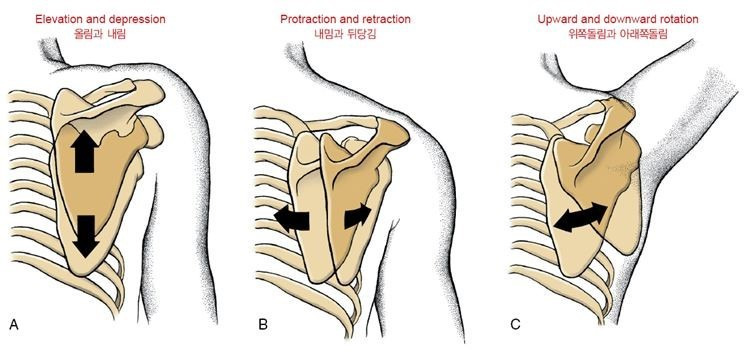

어깨가슴관절의 첫 번째 움직임은

"올림/내림"입니다. (그림 A)

어깨뼈를 으쓱하는 동작에서 복장빗장관절(SC)은

빗장뼈의 올림으로 일어나고

봉우리빗장관절(AC)에서는

약간의 어깨뼈 아래쪽 돌림이 일어나

어깨뼈가 거의 세로 상태를

유지할 수 있도록 해줍니다.

또한 돌림성 조절 운동을 통해

어깨뼈가 가슴우리의 만곡에 맞춰 위치하도록 도움을 줍니다.

내림은 올림의 반대로

빗장뼈가 내려가면서

어깨뼈가 약간 위쪽 돌림이 일어나

정상 자세로 돌아 오는 것을 말합니다.

두 번째 움직임은

"내밈/뒤당김"입니다. (그림 B)

복장빗장관절(SC)에서

내밈동작 일어나고 있는 빗장뼈의 경로를 따라

어깨뼈도 같이 움직입니다.

봉우리빗장관절(AC)에서는

안쪽 돌림이 일어나

내밈의 전체 범위를 조절하거나 보충할 수 있습니다.

어깨가슴관절(ST)에서의 내밈은

복장빗장관절과 봉우리빗장관절의

합성으로 일어나기 때문에

하나의 관절에서 운동능력 감소는

다른 관절에서 운동능력으로 보상되기에

세 관절 모두 제 기능을 할 수 있어야 기능의 제한이 생기지 않습니다.

뒤당김은 내밈의 동작과 반대로 일어나며

사물을 신체 쪽으로 당기는 동작을 예로 들 수 있습니다.

세 번째로는

"위쪽 돌림/아래쪽 돌림"입니다. (그림 C)

어깨가슴관절에서의 위쪽 돌림은

어깨를 완전 벌림 또는 완전굽힘시에 중요한 역할을 합니다!